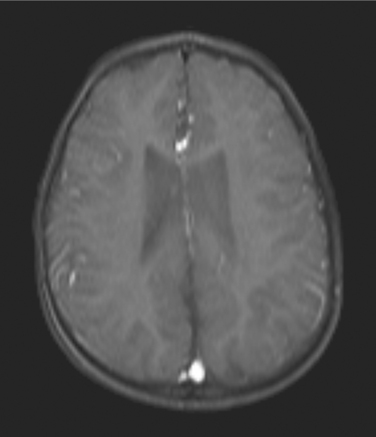

Until recently, interventricular hemorrhage (IVH) was the most common form of brain injury in the premature infant (Fig. 35-1). In recent years the incidence of IVH has declined from an incidence of 49% in very-low-birth-weight infants to 20% in the same population.35a As a result, periventricular white matter injury has become the more common cause of long-lasting brain injury in this population.

Figure 35-1 Magnetic resonance image of an interventricular hemorrhage with expansion of the lateral ventricles. This child was born at 26 weeks’ gestation and diagnosed with diplegic cerebral palsy. (Courtesy Allan Glanzman, Children’s Seashore House of the Children’s Hospital of Philadelphia, PA.)

Focal injury to the brain can also result from hemorrhage and ischemia, with the resulting collection of blood creating injury from direct mechanical pressure on the tissue and secondary ischemia. In the premature infant, hemorrhage of the germinal matrix (the cells from which the nervous system arises; in the adult, these cells, called ependymal cells, lie adjacent to the ventricular system) into the lateral ventricle (see Fig. 35-1) is a common cause of CP and can result in venous infarction of the periventricular area with a resulting cystic lesion in that portion of the brain.52